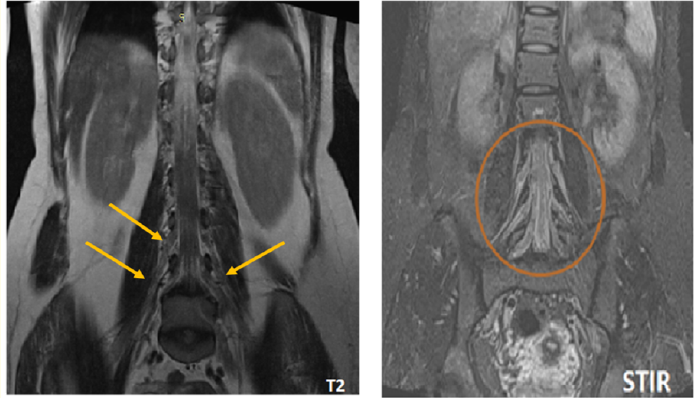

Imaging Utility in the Diagnosis of Dejerine-Sottas Disease: Case Report

Halfi Mohamed Ismail, Zahi Hiba, Fikri Meriem, Jiddane Mohamed and Touarsa Firdaous. 15(5): 88-92.